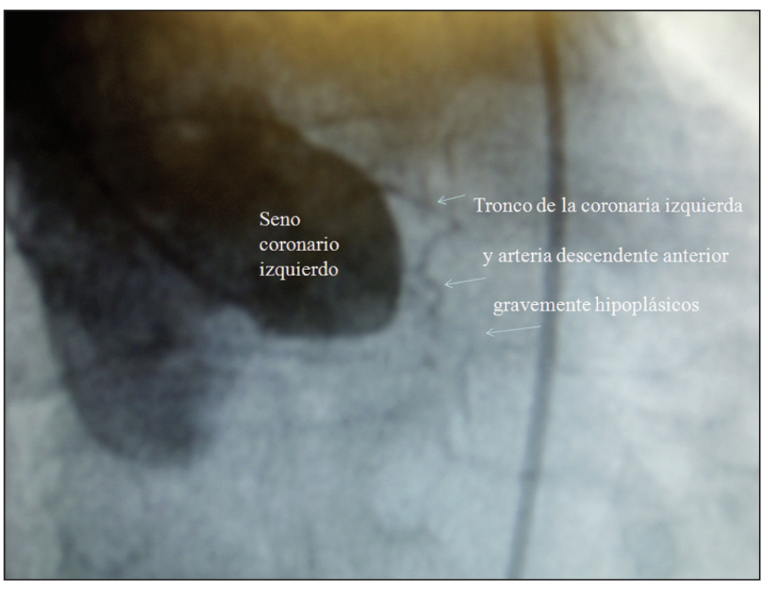

Síndrome coronario agudo secundario a hipoplasia grave del tronco y de la arteria descendente anterior

Las anomalías coronarias congénitas representan una rara entidad que infrecuentemente resulta la etiología subyacente de un síndrome coronario agudo. En esta presentación se describe el caso de una paciente de 48 años portadora de una hipoplasia grave del tronco y de la arteria descendente anterior asociada con un infarto agudo de miocardio sin elevación del segmento ST y se evalúan sus diagnósticos diferenciales, así como la decisión terapéutica. La paciente fue intervenida quirúrgicamente, con una evolución inicial favorable.